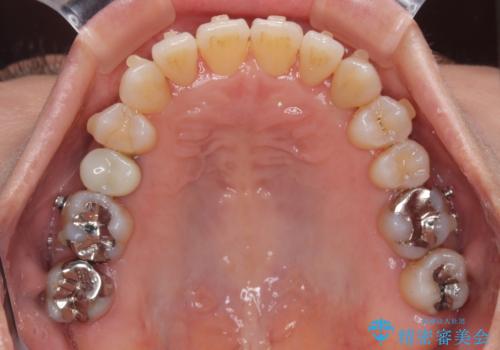

受け口と八重歯を改善 インビザライン矯正治療

- 前歯のデコボコや八重歯を治したいとのことで来院された患者様です。

受け口傾向の骨格であり、前歯はクロスバイトまたは切端咬合となっており、下顎を中心に歯列全体の後方移動を行い、IPR(歯と歯の間を削る)によってデコボコが解消するように設計し、インビザラインにより治療を行うこととしました。